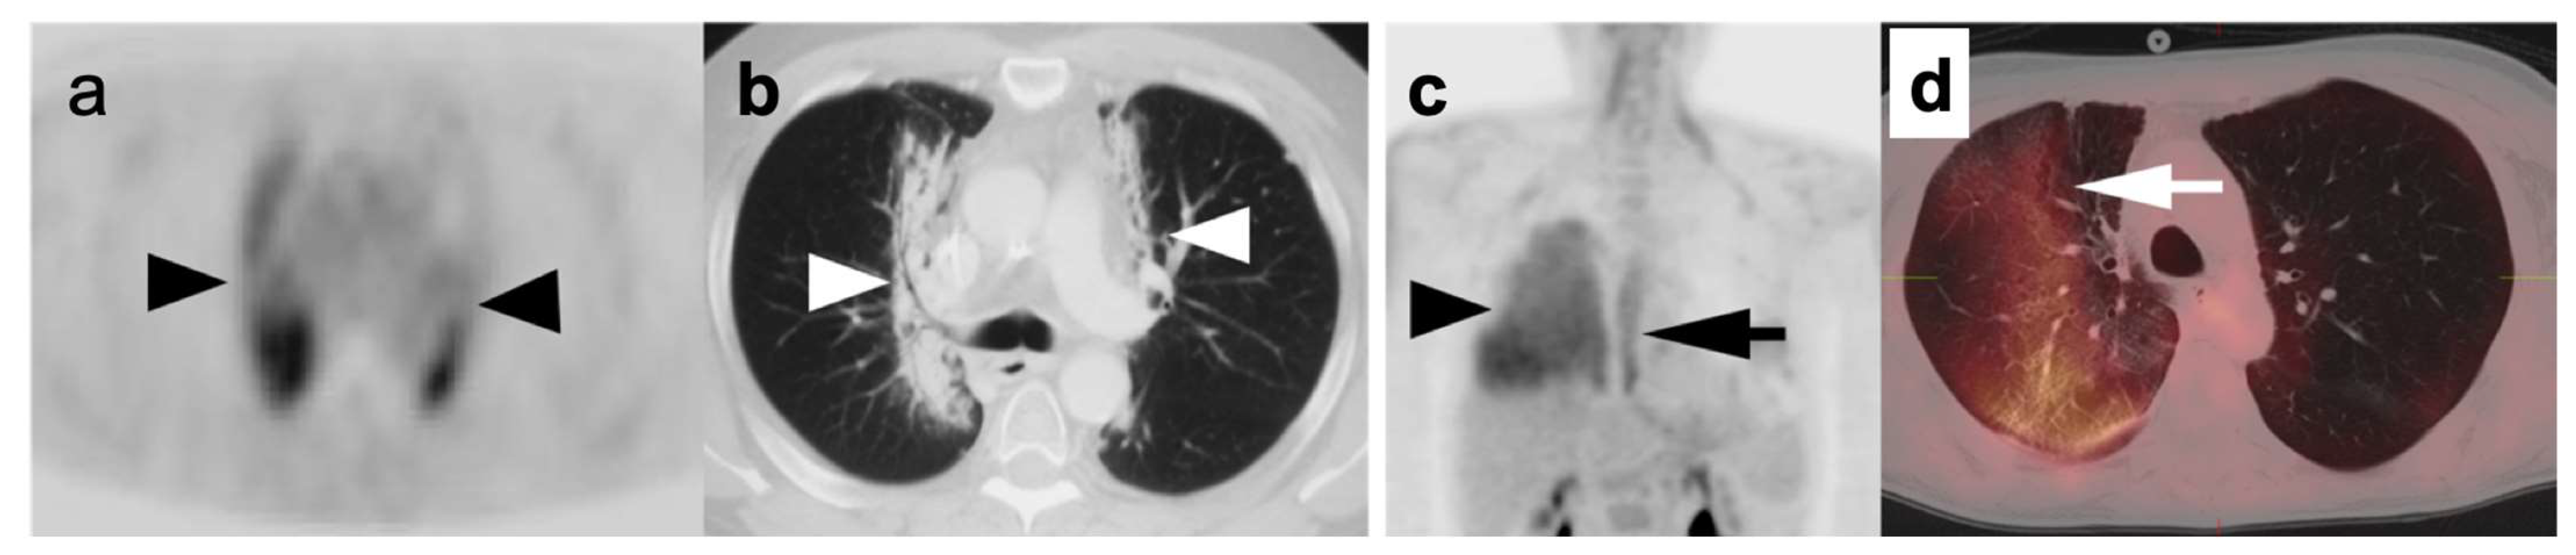

Chronic or acute inflammatory and granulomatous processes such as sarcoidosis are well-known causes of hypermetabolic lymphadenopathy within the mediastinum and hilar regions. Prior granulomatous disease is often associated with calcifications within the nodes and with associated pulmonary nodules, some of which may be calcified. Within the mediastinum and hila, granulomatous disease typically assumes a balanced, symmetrical distribution, whereas adenopathy due to lung cancer is typically more ipsilateral to the side of the primary tumor (Figure 2). However, histologic evaluation could be necessary in differentiating this systemic inflammatory process from advanced neoplastic disease with bilateral mediastinal or hilar hypermetabolic lymphadenopathy. Reactive processes to foreign material within the lung parenchyma or pleura, such as silica or talc, or within the nodes in the hilar region or mediastinum, can mimic malignant processes (Figure 3) [6]. Similar false positive findings can be encountered with acute infective processes such as Coccidioidomycosis as well as various mycobacterial infections, both of which present with similar pulmonary manifestations. The acute phase of these infections and other viral, bacterial, or fungal pulmonary infections demonstrate hypermetabolic parenchymal or nodal lesions on FDG PET-CT and may mimic primary or metastatic lung malignancy (Figure 4) [7].

A number of pitfalls can be a hindrance in the assessment of SPNs with FDG PET-CT including inflammatory conditions or infections such as bacterial or fungal infections; and granulomatous entities such as tuberculosis, sarcoidosis, and histoplasmosis, all of which exhibit increased metabolic activity [12,24]. Additionally, FDG PET-CT can result in false-negative studies due to limited spatial resolution of PET cameras, resulting in partial volume effects that limit characterization of very small nodules. Additional causes of false-negative scans are lepidic-type adenocarcinoma (which may be low in metabolic activity), typical bronchial carcinoid tumors, and metastatic disease from tumors that may be low in metabolic activity (such as renal cell carcinoma, some lower grade sarcomas, and some testicular cancers (Figure 7). As such, a lung nodule that is not hypermetabolic on FDG PET-CT must nonetheless be followed by CT according to conventional Fleischner criteria.